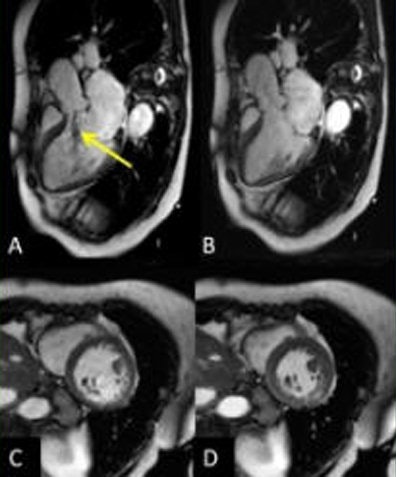

The study team implemented its single breath-hold multislice CS cine sequence on a 1.5-tesla MR system (Magnetom Aera, Siemens Healthcare), acquiring three long-axis and four short-axis slices over 14 heartbeats in a single breath-hold. Temporal and spatial resolution was 30 msec and 1.5 x 1.5 mm2, respectively. Data were analyzed using Argus 4DVF software (Siemens Healthcare).

The CS acquisitions maintained high image quality in 94% of subjects, maintaining qualitative accuracy in LV systolic function (above) and with excellent correlation (r = 0.96, slope = 0.97, p < 0.00001). Finally, intra-/interobserver agreement for all CS parameters was good (slopes: 0.93-1.06, r: 0.90-0.99), the group reported.